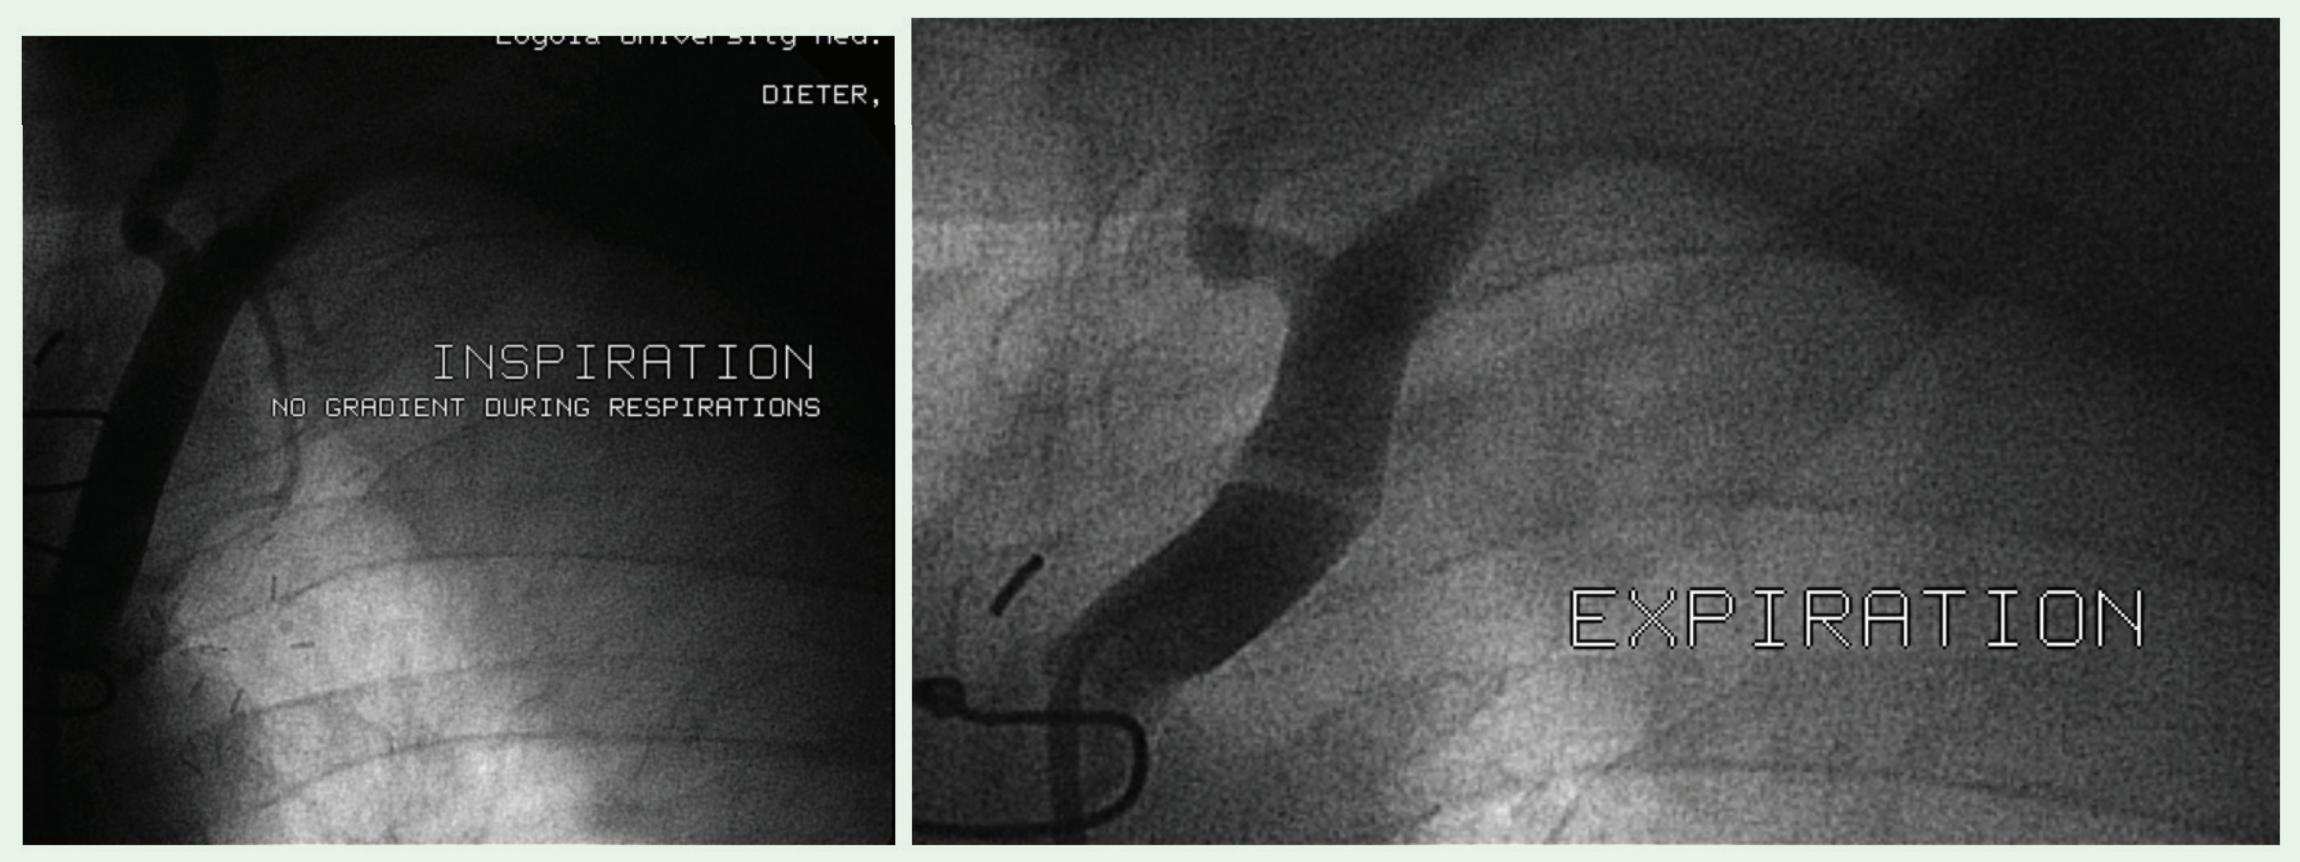

The left subclavian artery is generally the third branch of the aortic arch. It extends from the aorta to the outer edge of the first rib, at which point it is termed the axillary artery. The left subclavian artery can be divided into three portions based on the scalenus anterior muscle. The ascending, or first portion, ascends to the base of the neck before angling towards the medial aspect of the scalenus anterior muscle. With advancing age, the aorta becomes angulated, tortuous, and elongated. Consequently, the normal anatomy of the left subclavian may become distorted. With these anatomical changes, the relatively tethered aorta at the ligamentum arteriousum may transmit more respiratory motion of the aorta to the arch vessels, particularly the left subclavian artery. With inspiration, the aorta and the proximal left subclavian may become unfolded. It is unlikely that the use of the LIMA as a bypass graft contributed to the proximal left subclavian artery folding during expiration.

We describe two cases of patients who had dynamic ascending left subclavian artery kinking. Angiography was indicated for the evaluation of the LIMA bypass graft in both cases. The folding was initially diagnosed when the guidewire was unable to traverse the proximal (not ostial) left subclavian. Interestingly, although both demonstrated physical obstruction to the guidewire, neither case had a translesional gradient during respirations. This would suggest that the anatomic kinking did not have physiological consequences, and these lesions should not be invasively treated. Aside from the anatomic stenosis without physiological consequence, these cases highlight the forces on the proximal left subclavian artery. This region has previously been thought to be a relatively fixed and immobile arterial segment. The clinical consequences of the forces imparted on this segment following endovascular stent implantation are unknown. There are no reported cases of left subclavian artery stent fracture. However, it is doubtful that this has been adequately evaluated. The restenosis rates for subclavian artery stenting are low, with five year patency usually above 85%,3,4 but the cases of restenosis may be related to the regular forces transmitted to this region.

The ascending portion of the left subclavian artery is not a fixed arterial segment. There is considerable movement during respiration, with kinking seen during expiration, and relief with inspiration. Clinicians should be aware of this process, both during diagnostic catheterization in making the diagnosis of left subclavian artery stenosis as well as during endovascular treatment of such. Prospective studies are underway to determine the prevalence and clinical significance of this finding.